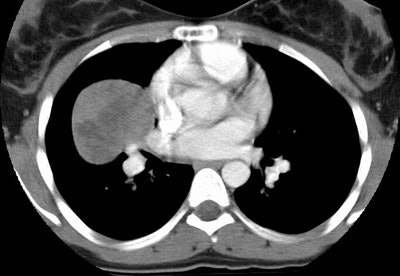

The images demonstrate an enhancing soft tissue mass within the right lung. The mass has areas of slightly decreased attenuation best appreciated following IV contrast administration. (Click images to enlarge)

Post contrast CT with enhancement and areas of decreased attenuation: